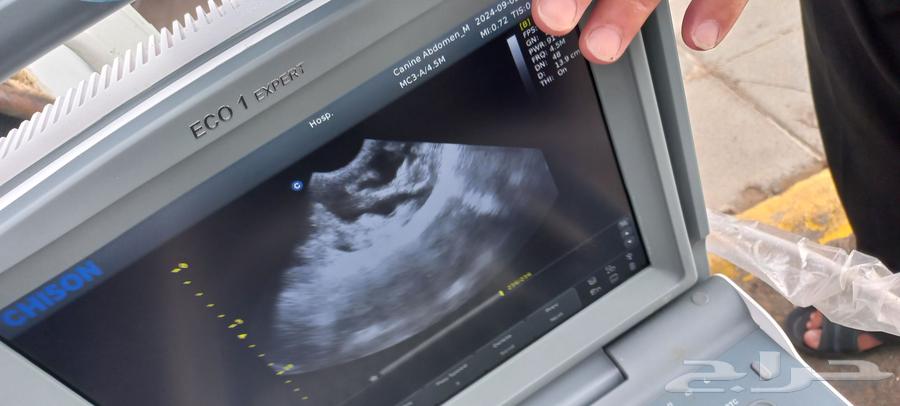

We offer to our respected halal community the pregnancy detection service for sheep and goats using the latest ultrasound devices, with God's grace ensuring the highest accuracy and at reasonable prices. The price is determined according to distance and quantity. Special prices for large quantities